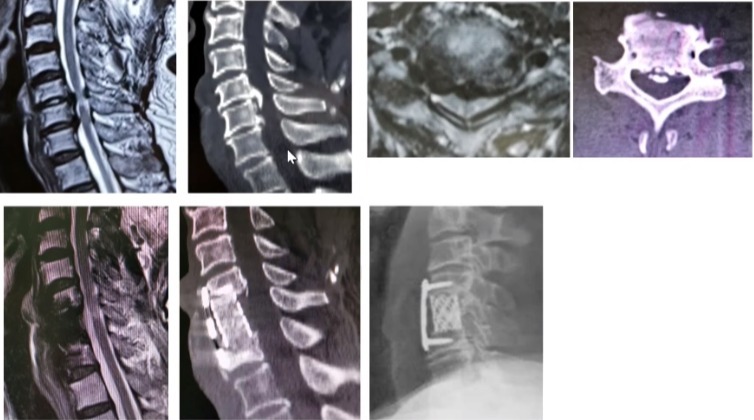

后路单开门

后路单开门:门轴断裂

后路减压固定融合

后路C5神经根麻痹